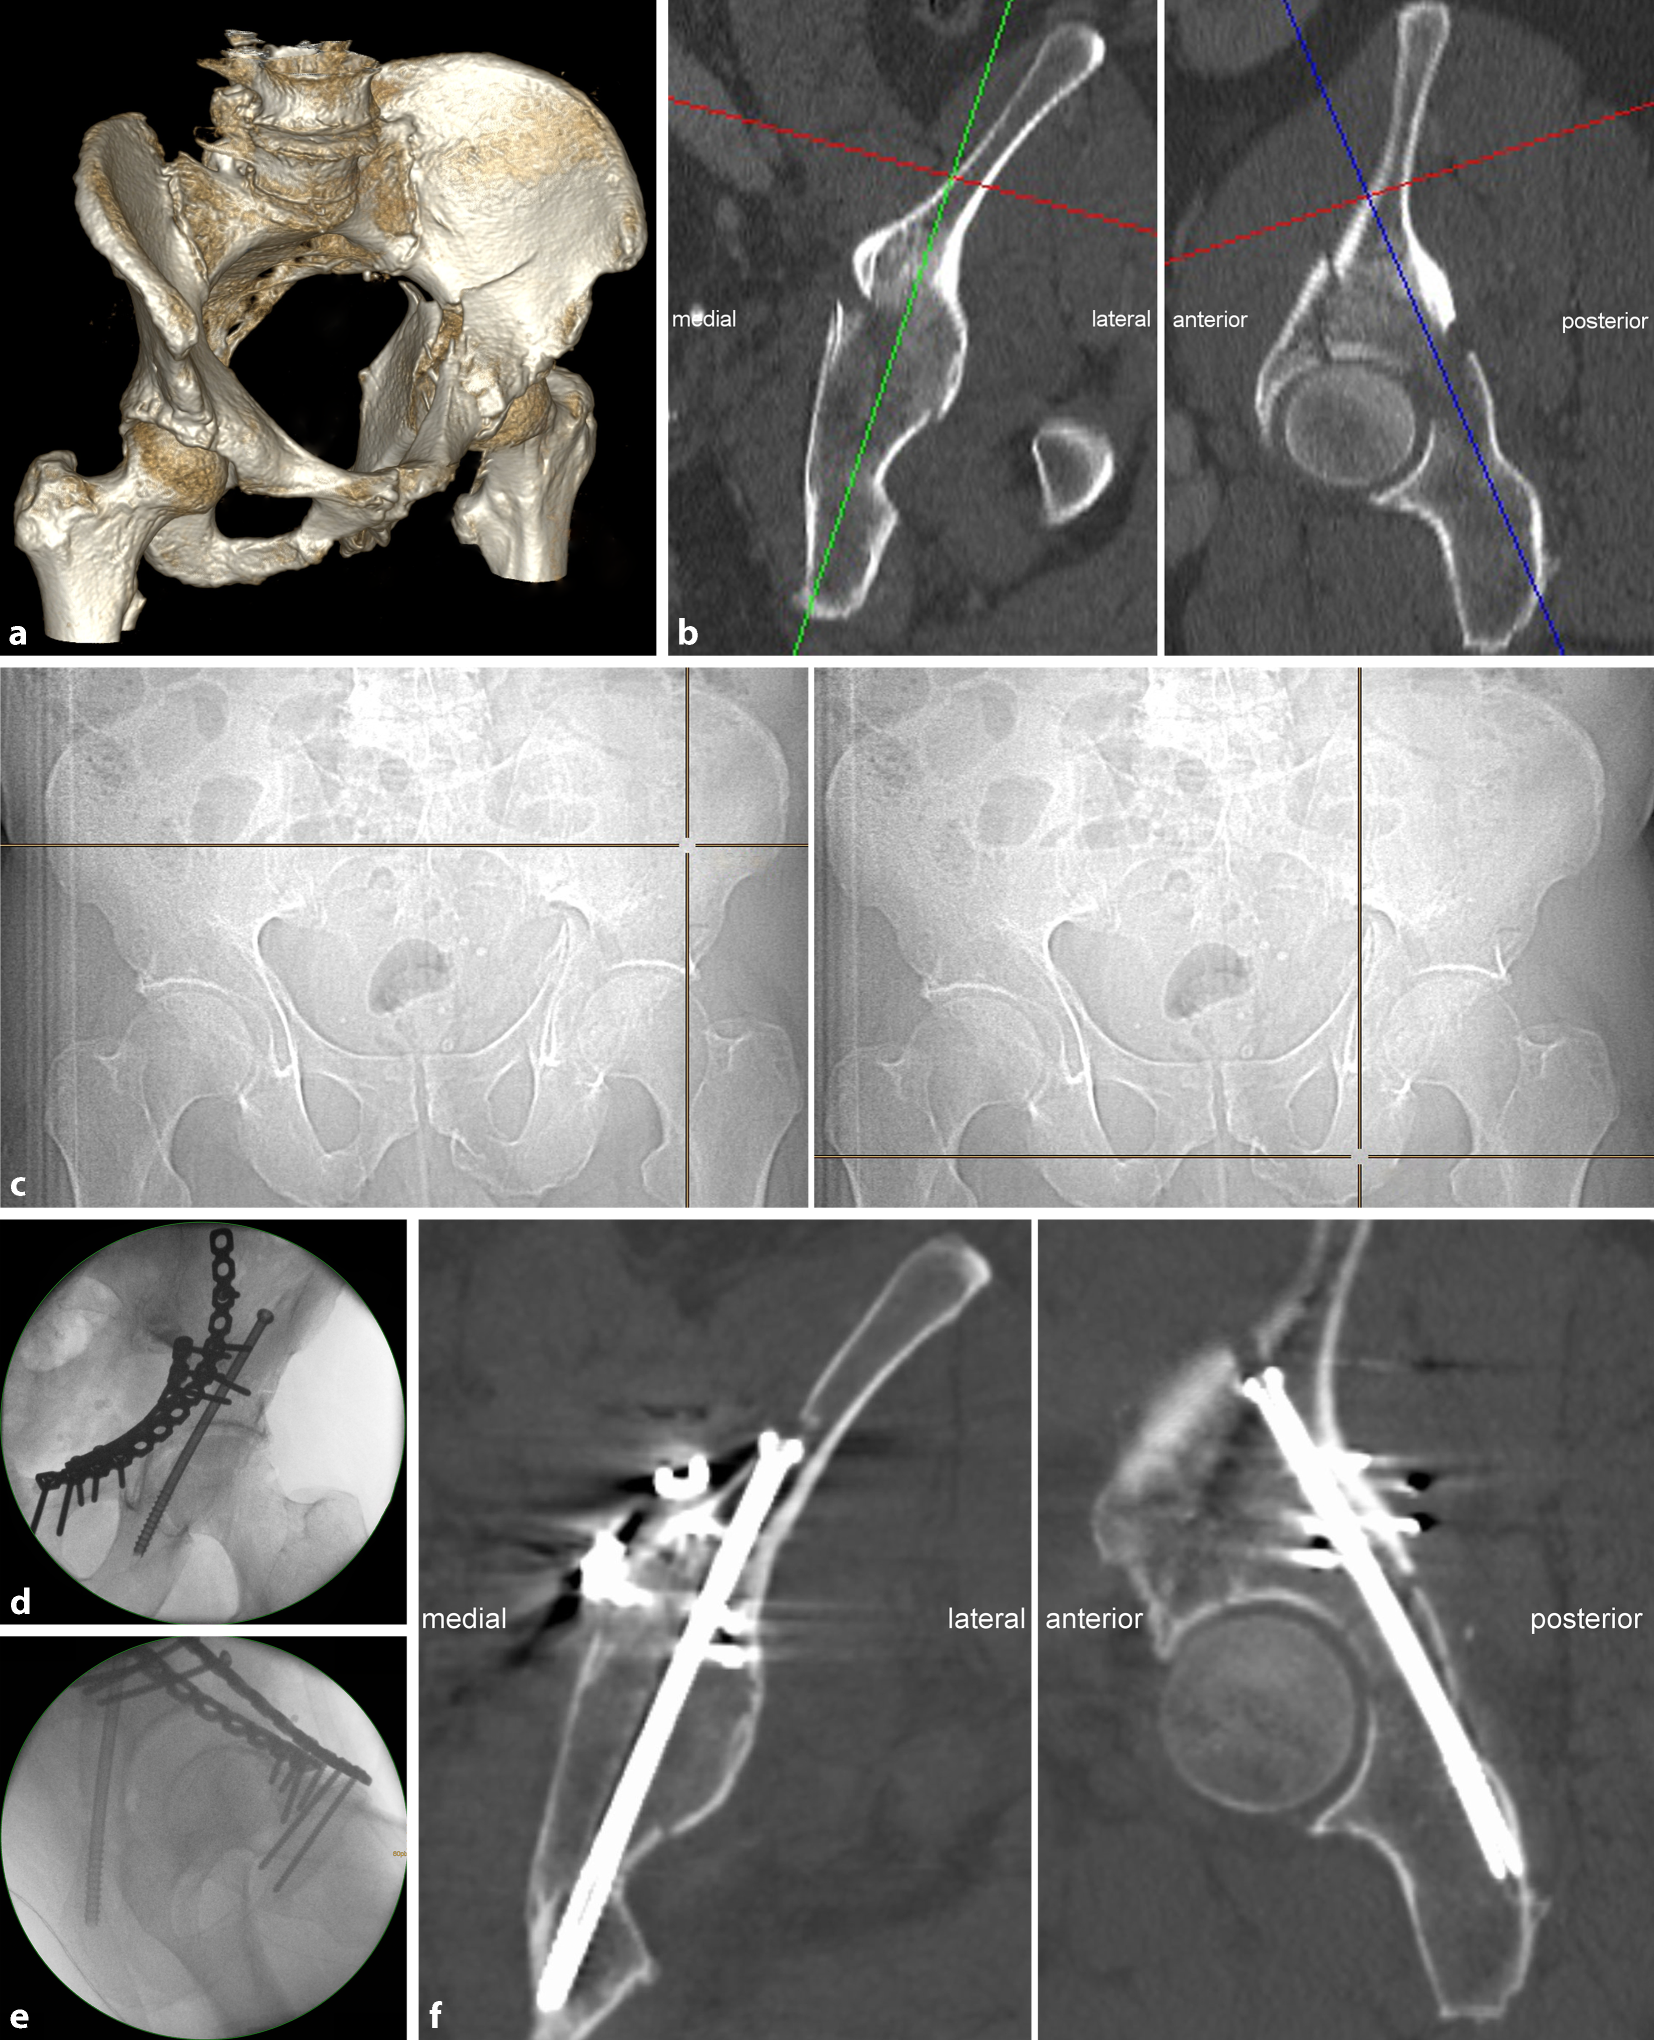

Fig. 2

Preoperative assessment of the osseous corridor and ideal posterior column screw trajectory. We highly recommend to assess the ideal posterior column screw trajectory using the uninjured contralateral acetabulum because screw trajectory analysis is easier and more precise in absence of fracture lines and displacement. The uninjured contralateral acetabulum can be reliably used as a template for preoperative planning as the left and right posterior column anatomy (screw insertion angles, screw starting point and screw length) do not significantly differ within the same pelvis (see Results). In case of no or only minor displacement, however, preoperative planning may be also performed on the injured side. The starting point of the posterior column screw is located in the transition zone between the supraacetabular region and the iliac wing on the inner cortex of the iliac bone. The screw trajectory is oriented from cranial–anterior–lateral to caudal–posterior–medial (a, b). The ideal starting point and screw trajectory are assessed by using native axial CT images and a two-dimensional multiplanar software reconstruction tool. Therefore, the axes of coordinates are translated and the axes itself rotated to assess the ideal entry point and screw trajectory. In the present case, the medial angle of the ideal posterior column screw trajectory is 14° to the sagittal plane (a) with a maximum screw length of 130 mm from the starting point to the end point (cortex of the sciatic tuber). Furthermore, the posterior angle of this screw trajectory is 28° to the coronal plane (b) and obviously shows the same maximum screw length in this second reformation plane

Fig. 3

Estimation of the starting point and endpoint of the ideal screw trajectory. This is one of the major challenges in fluoroscopically controlled posterior lag screw fixation. The preoperative planning is performed using multiplanar CT reformations in all three dimensions. The intraoperative application, however, is performed using two-dimensional (2D) fluoroscopic control. The CT scout image is used to facilitate this transition. It is a low-dose pelvic X‑ray routinely obtained during standard CT imaging, which is usually performed in a standard supine position and thus corresponds to intraoperative positioning of the patient. Pads or pillows supporting the lumbosacral region modify the pelvic tilt and should therefore not be used intraoperatively. Software tools allow for a real-time localization of any arbitrary CT point in the scout view (“LiveSync” feature). Thus, the surgeon is able to transfer the ideal screw starting (a) and endpoint (b) identified in multiplanar CT reformations to the 2D anterior–posterior (ap) view scout image. This greatly facilitates identification of the ideal localization of the screw starting and end point (and therefore of the screw trajectory) in the intraoperative pelvic ap view